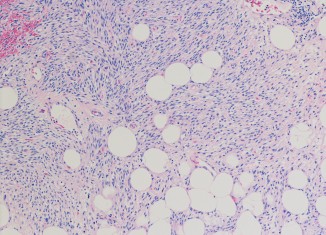

Lipomas are generally harmless deposits of fat under the skin and Lipomas are mostly seen around the neck, shoulders, back, abdomen, arms and thighs,...

Before we go into the details of products that can be used for curing Lipoma, we should first know what the Lipoma is. Lipomas...